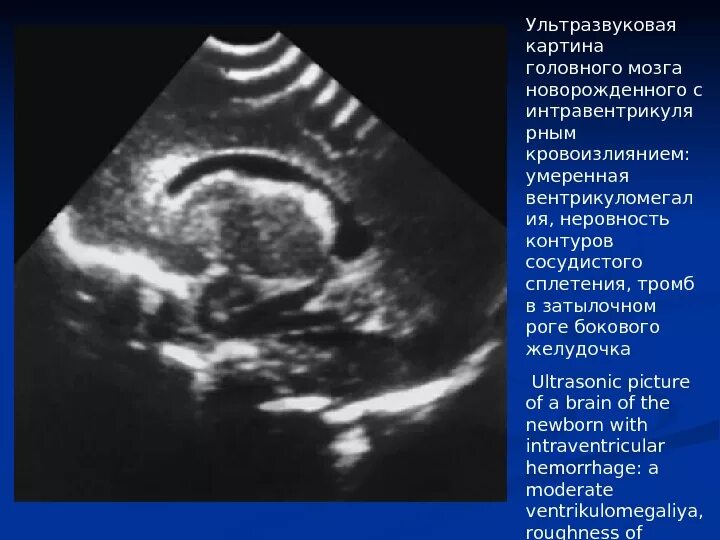

Кровоизлияние в мозг у новорожденного степени